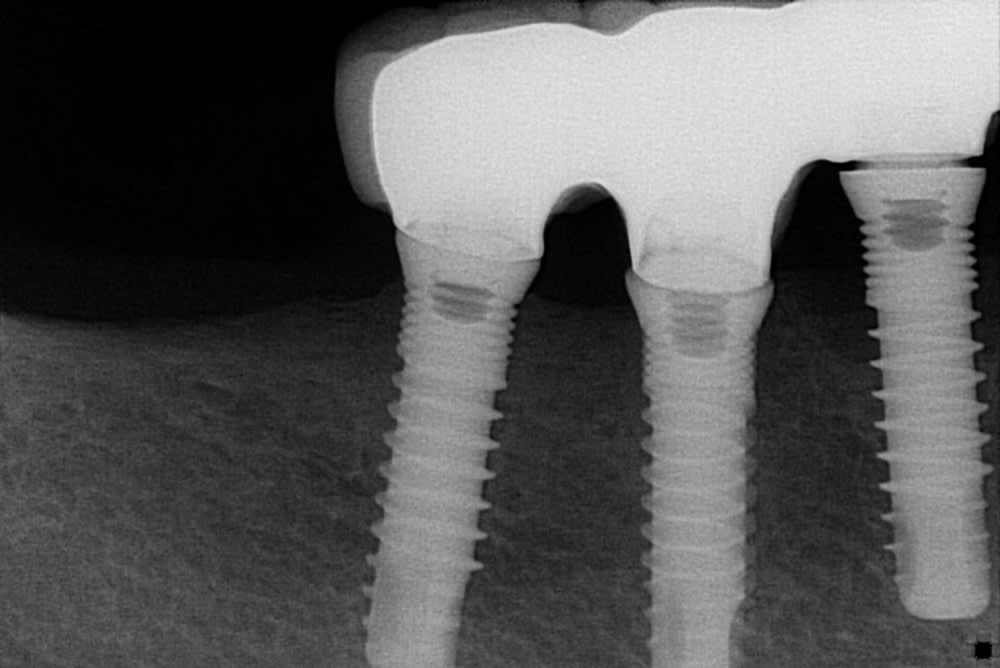

pourriez-vous m'aider dans l'identification de ces implants?

EVL C Serf (maintenant globalD)

https://www.spotimplant.com/fr/implants-dentaire/globald/evl-c